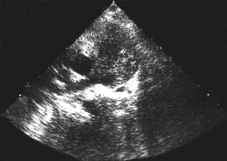

Rabdomiomas múltiples en recién nacido con hidrops.

Imagen con Doppler. |